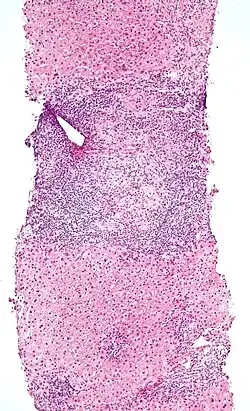

Low-magnification micrograph of PBC, H&E stain -

On microscopic examination of liver biopsy specimens, PBC is characterized by chronic, nonsuppurative inflammation, which surrounds and destroys interlobular and septal bile ducts. These histopathologic findings in primary biliary cholangitis include:[32]

- Inflammation of the bile ducts, characterized by intraepithelial lymphocytes

- Periductal epithelioid granulomas.

- Proliferation of bile ductules

- Fibrosis (scarring)

The Ludwig and Scheuer scoring systems have historically been used to stratify four stages of PBC, with stage 4 indicating the presence of cirrhosis. In the new system of Nakanuma, the stage of disease is based on fibrosis, bile duct loss, and features of cholestasis, i.e. deposition of orcein-positive granules, whereas the grade of necroinflammatory activity is based on cholangitis and interface hepatitis. The accumulation of orcein-positive granules occurs evenly across the PBC liver, which means that staging using the Nakanuma system is more reliable regarding sampling variability.